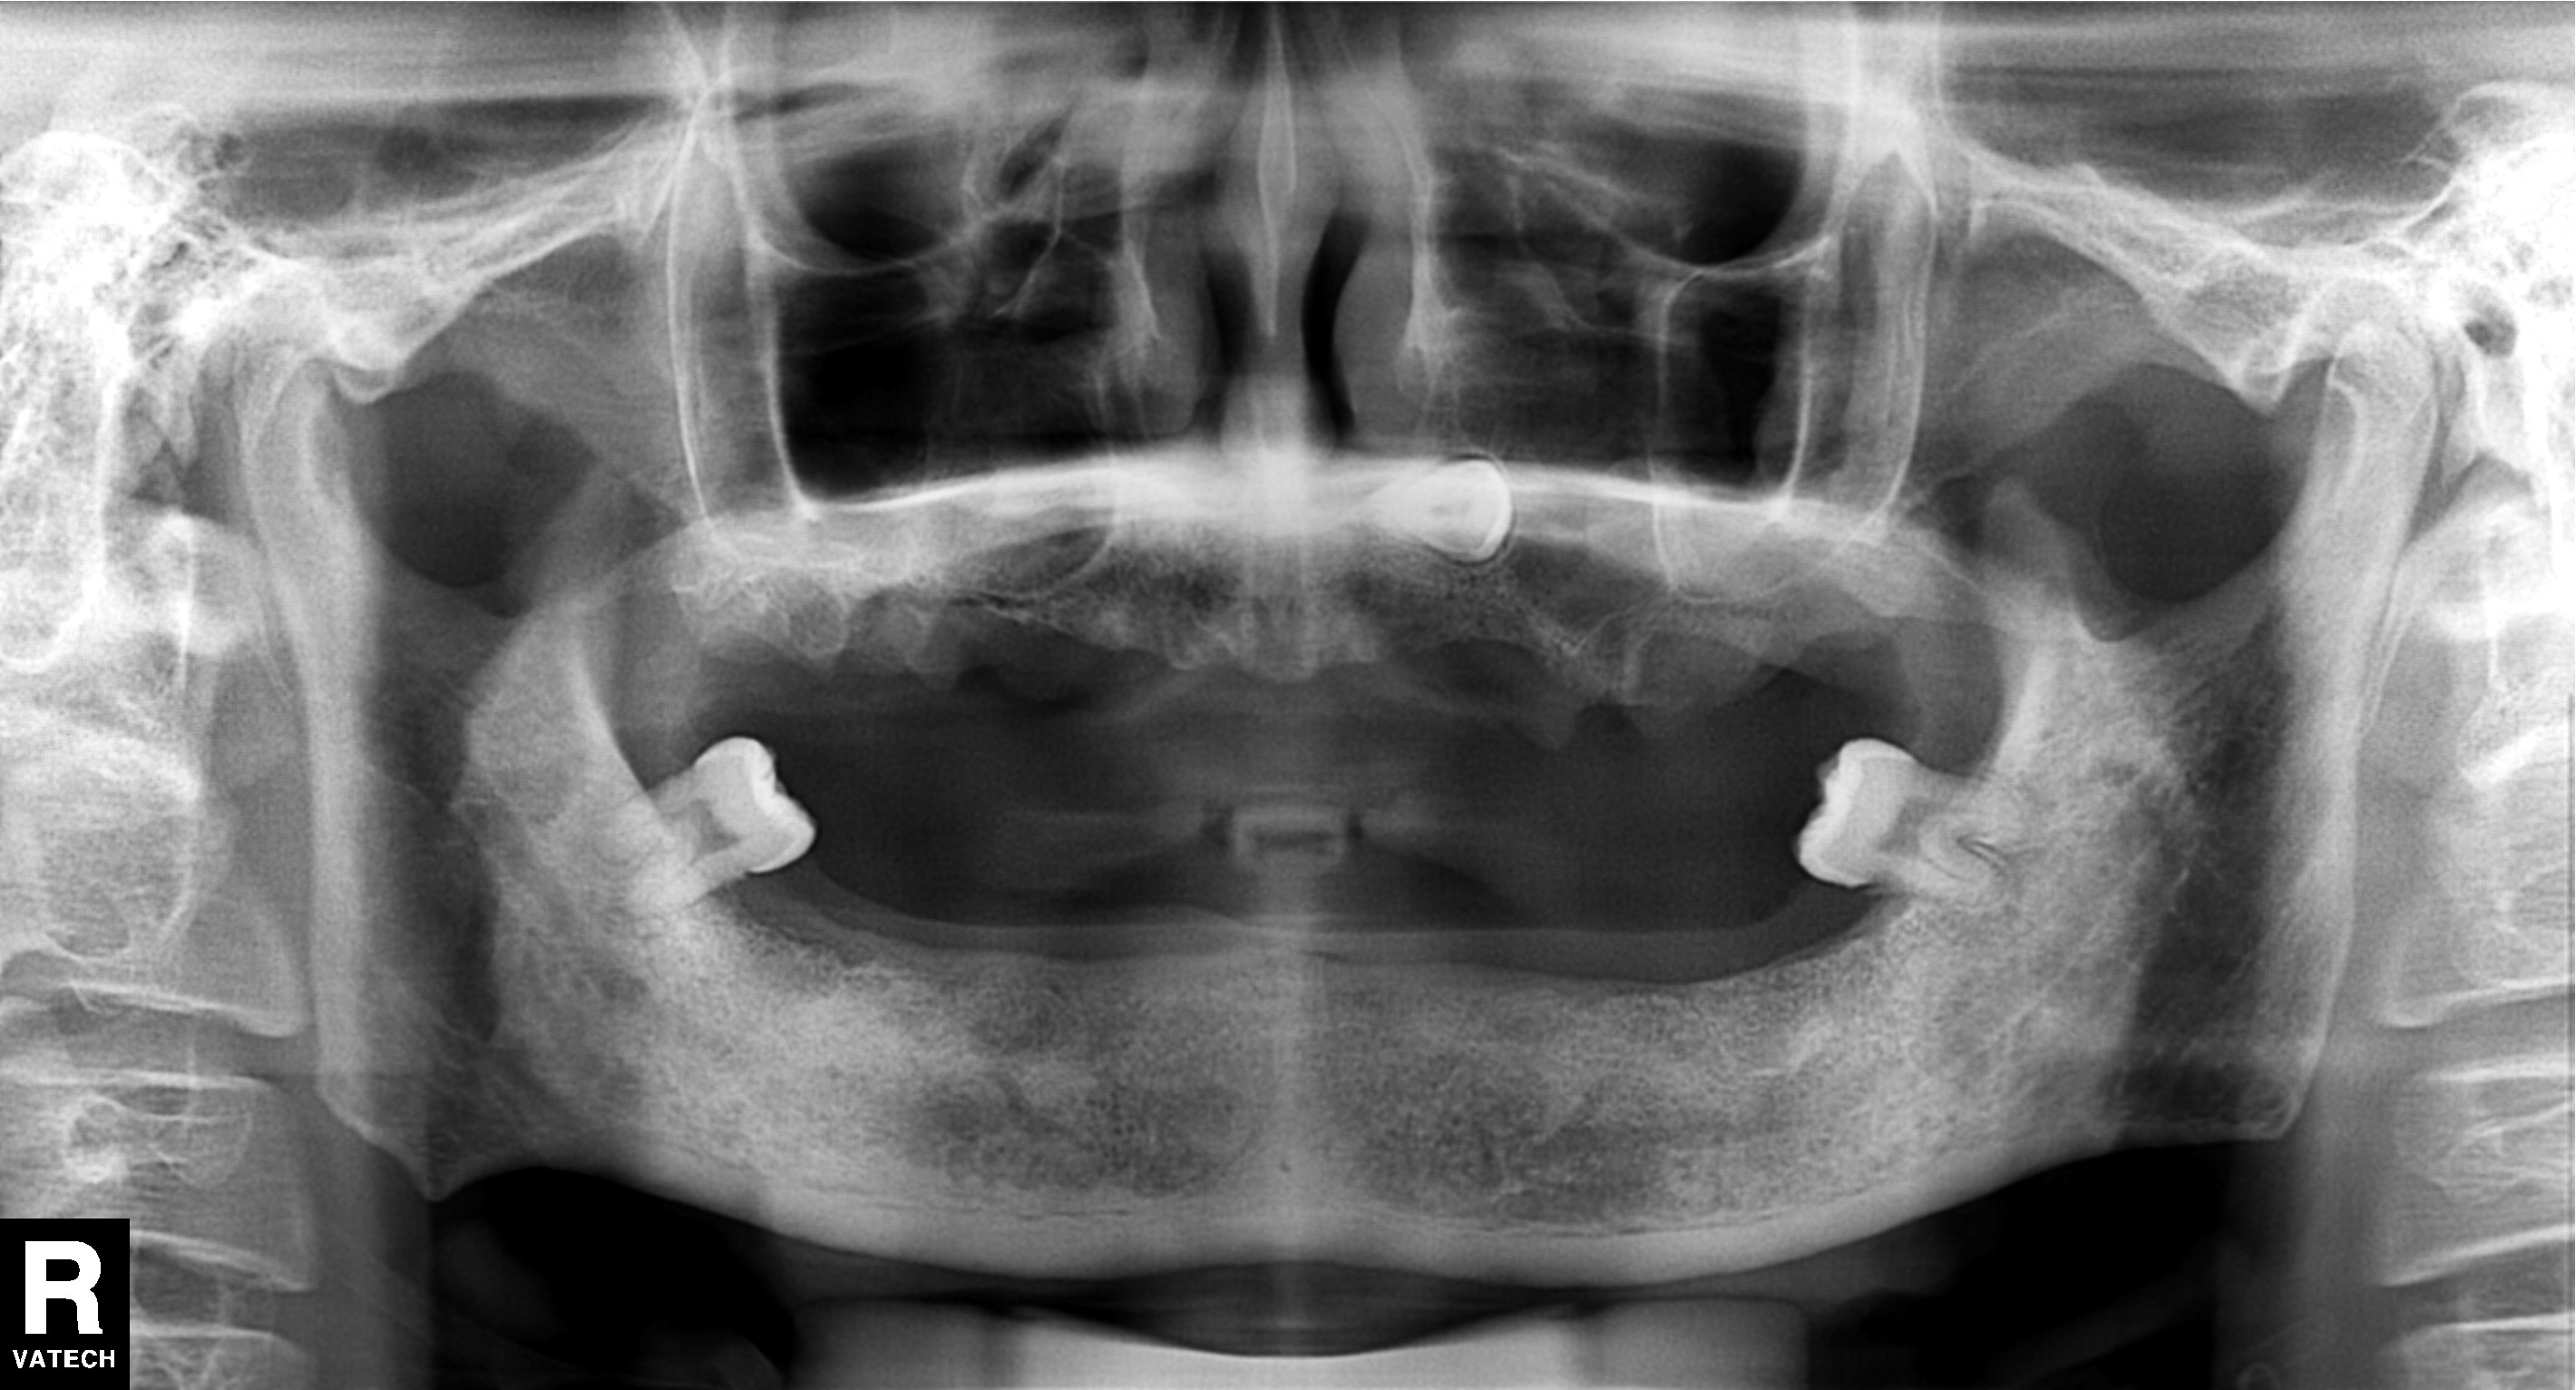

大家想象的全口種植牙是這樣的

術前全口隻剩兩(liang) 顆牙